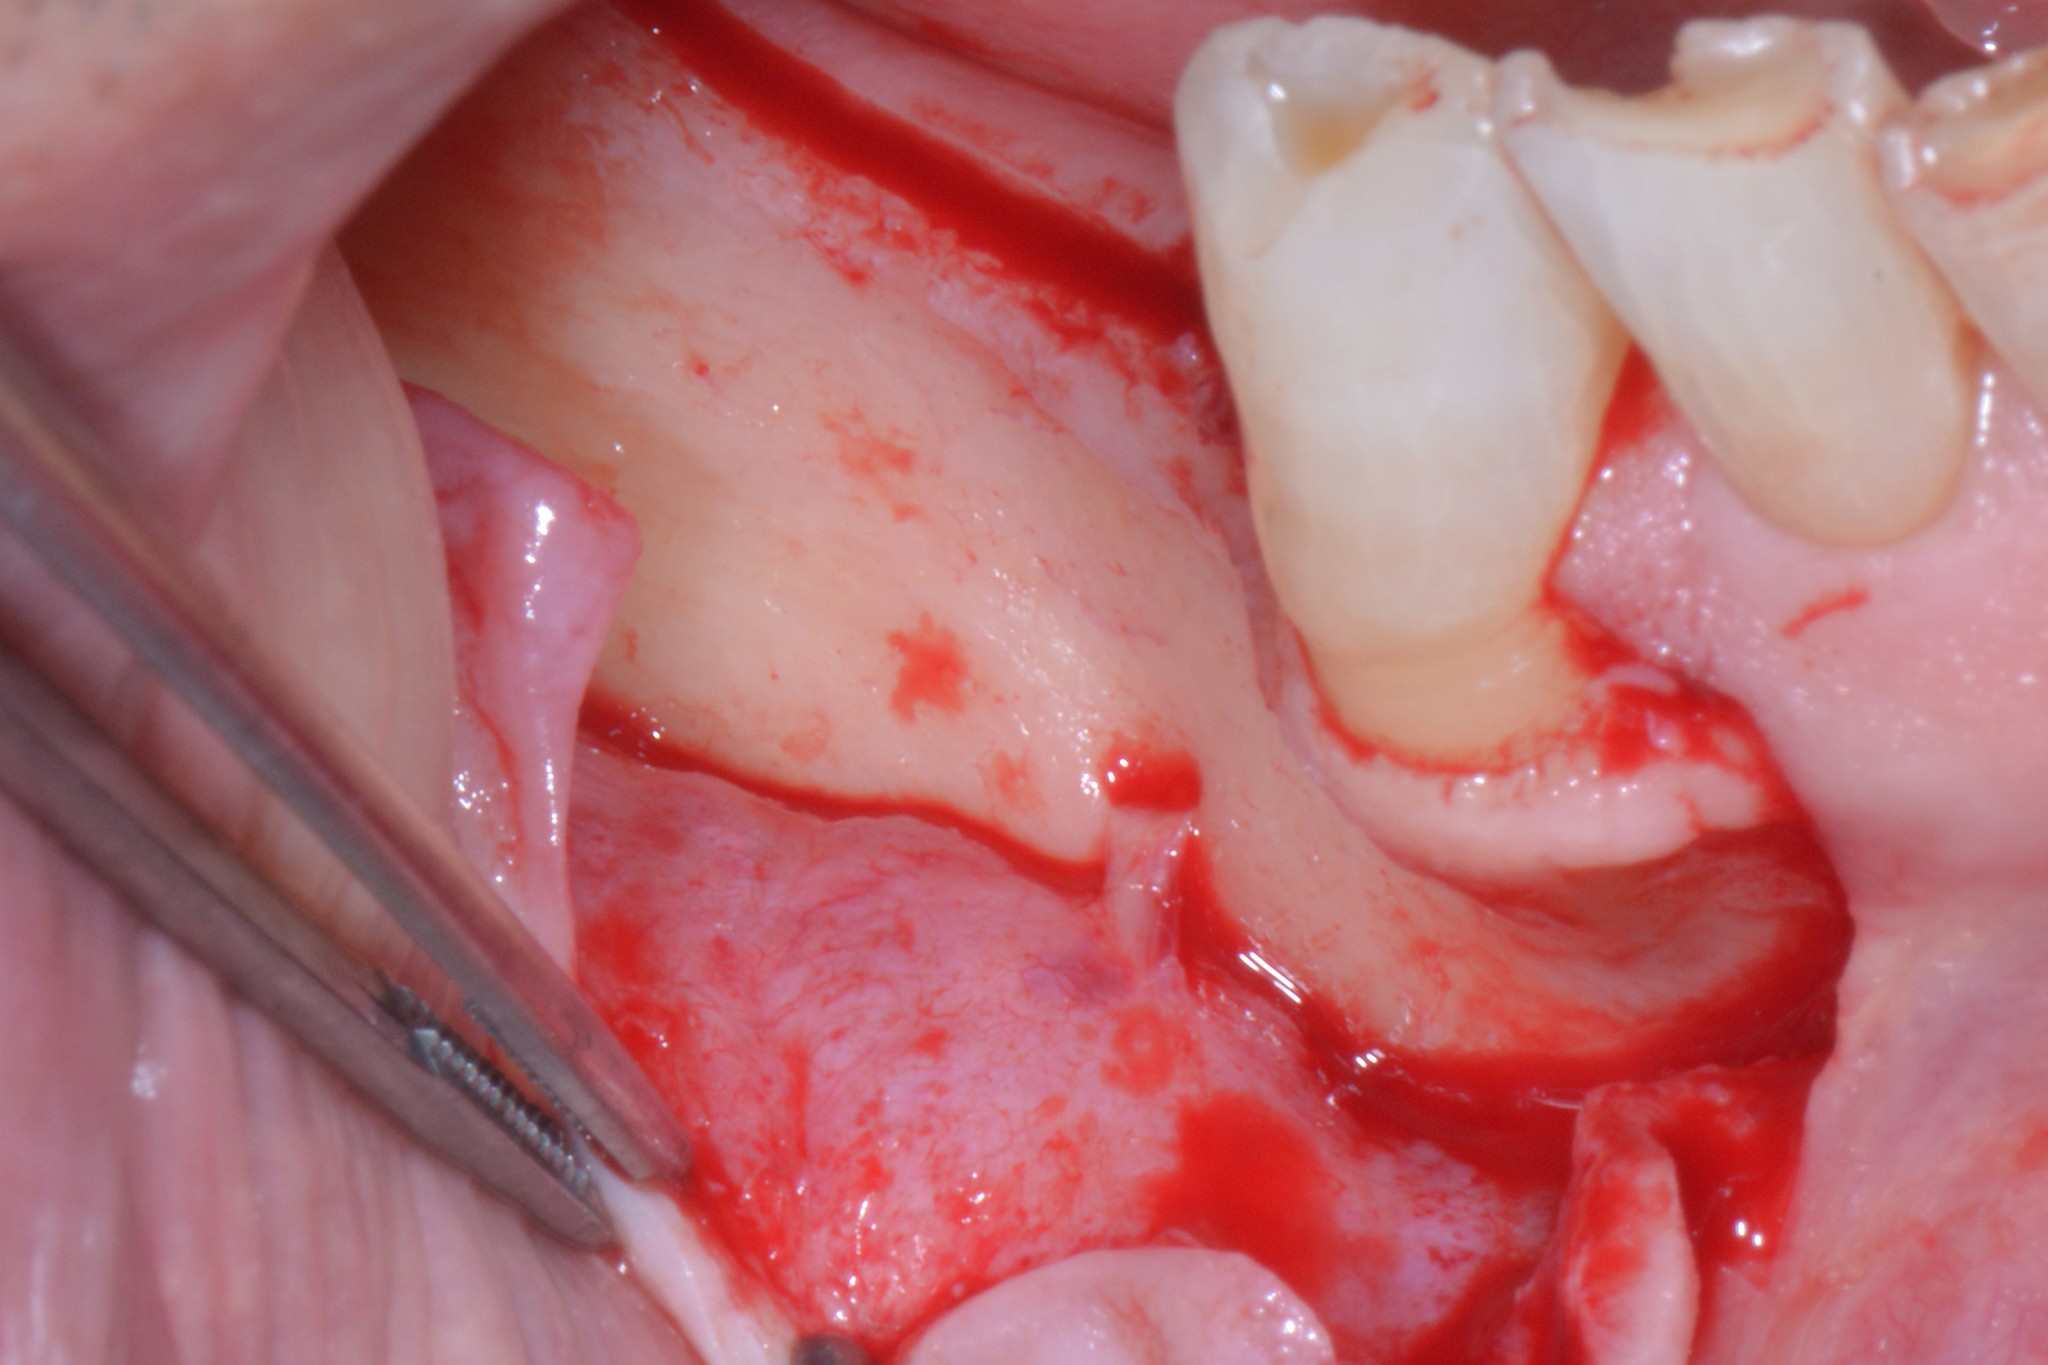

Solo adesso che il caso ci è ben chiaro possiamo iniziare il nostro intervento avendo le idee ben chiare, un paziente ben informato e una buona probabilità di non fare cazzate.

Se lo lasciamo lì ovviamente non possiamo ricostruire un bel niente, ti faccio allora vedere come ho risolto io la situazione, ma a parte il tecnicismo chirurgico spero che il messaggio ti sia chiaro: